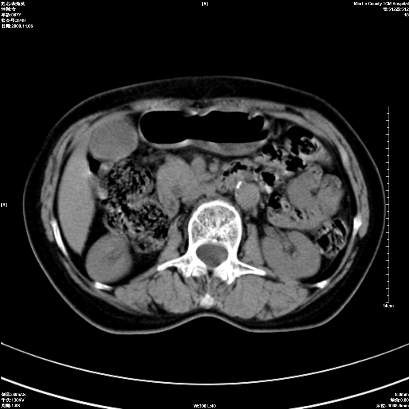

以下是引用卜一在2008-11-6 15:58:00的发言:[br]胰头略增大,胆总管扩张,末端渐行性狭窄。多考虑:胰头癌!建议增强!

以下是引用huangyinshan在2008-11-6 16:32:00的发言:[br]胰头略增大,胆总管扩张,末端渐行性狭窄。多考虑:胰头癌!建议增强!